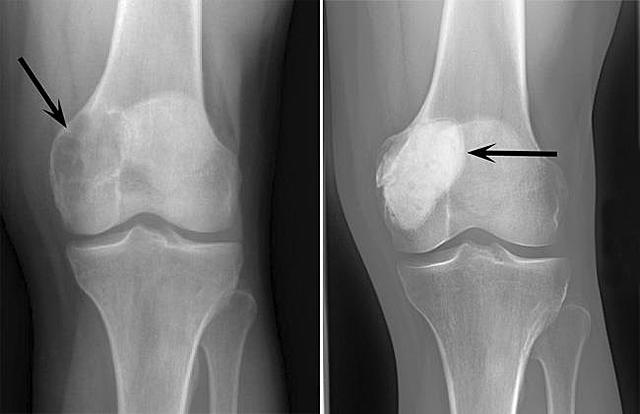

on february of my freshman year, i got a surgery to have an oversized growth removed from the growth plate in my knee. the growth was located on my tibia behind my patella (knee cap) and it caused so much excruciating paint that i could barley walk. it was a huge impact on my life already and the fact that i had to get a surgery around this time made it even worse. i missed lacrosse tryouts because of it, im a little shorter than i was supposed to be because of it, and the news scared us.